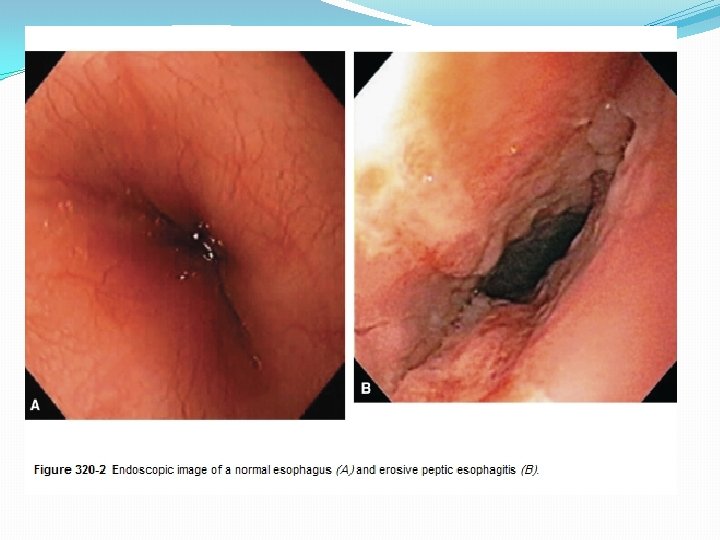

4. Endoscopy : allows diagnosis of erosive esophagitis and complications such as strictures or Barrett esophagus; biopsies can be taken. 5. Laryngotracheobronchoscopy : posterior laryngeal inflammation and vocal cord nodules. 6. Empirical antireflux therapy